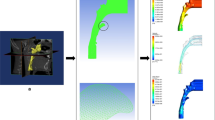

Three-dimensional reconstruction

Surface generation and meshing

The 14 3D models reconstructed in Mimics21.0 were imported into Geomagic studio 12.0 software in STL format, and the models were optimized by denoising, smoothing, accurate surface remodeling, and fitting surface remodeling. The obtained results were imported into Fluent pre-processing software ICEM-CFD (Ansys, Canonsburg, PA) in IGES format, the geometric model boundaries were created, the closed surface was generated, and finally the finite element mesh was divided to control the total mesh number of approximately 2 million to 3 million. The mesh minimum cell was a tetrahedral cell with a volume greater than 0 and no negative volume mesh, which was exported in MSH format.

Air flow simulation

Simulation of nasal cavity and sinus irrigation

Instantaneous volume fraction of the nasal cavity and sinus irrigation after Draf in adults with well-developed frontal sinus